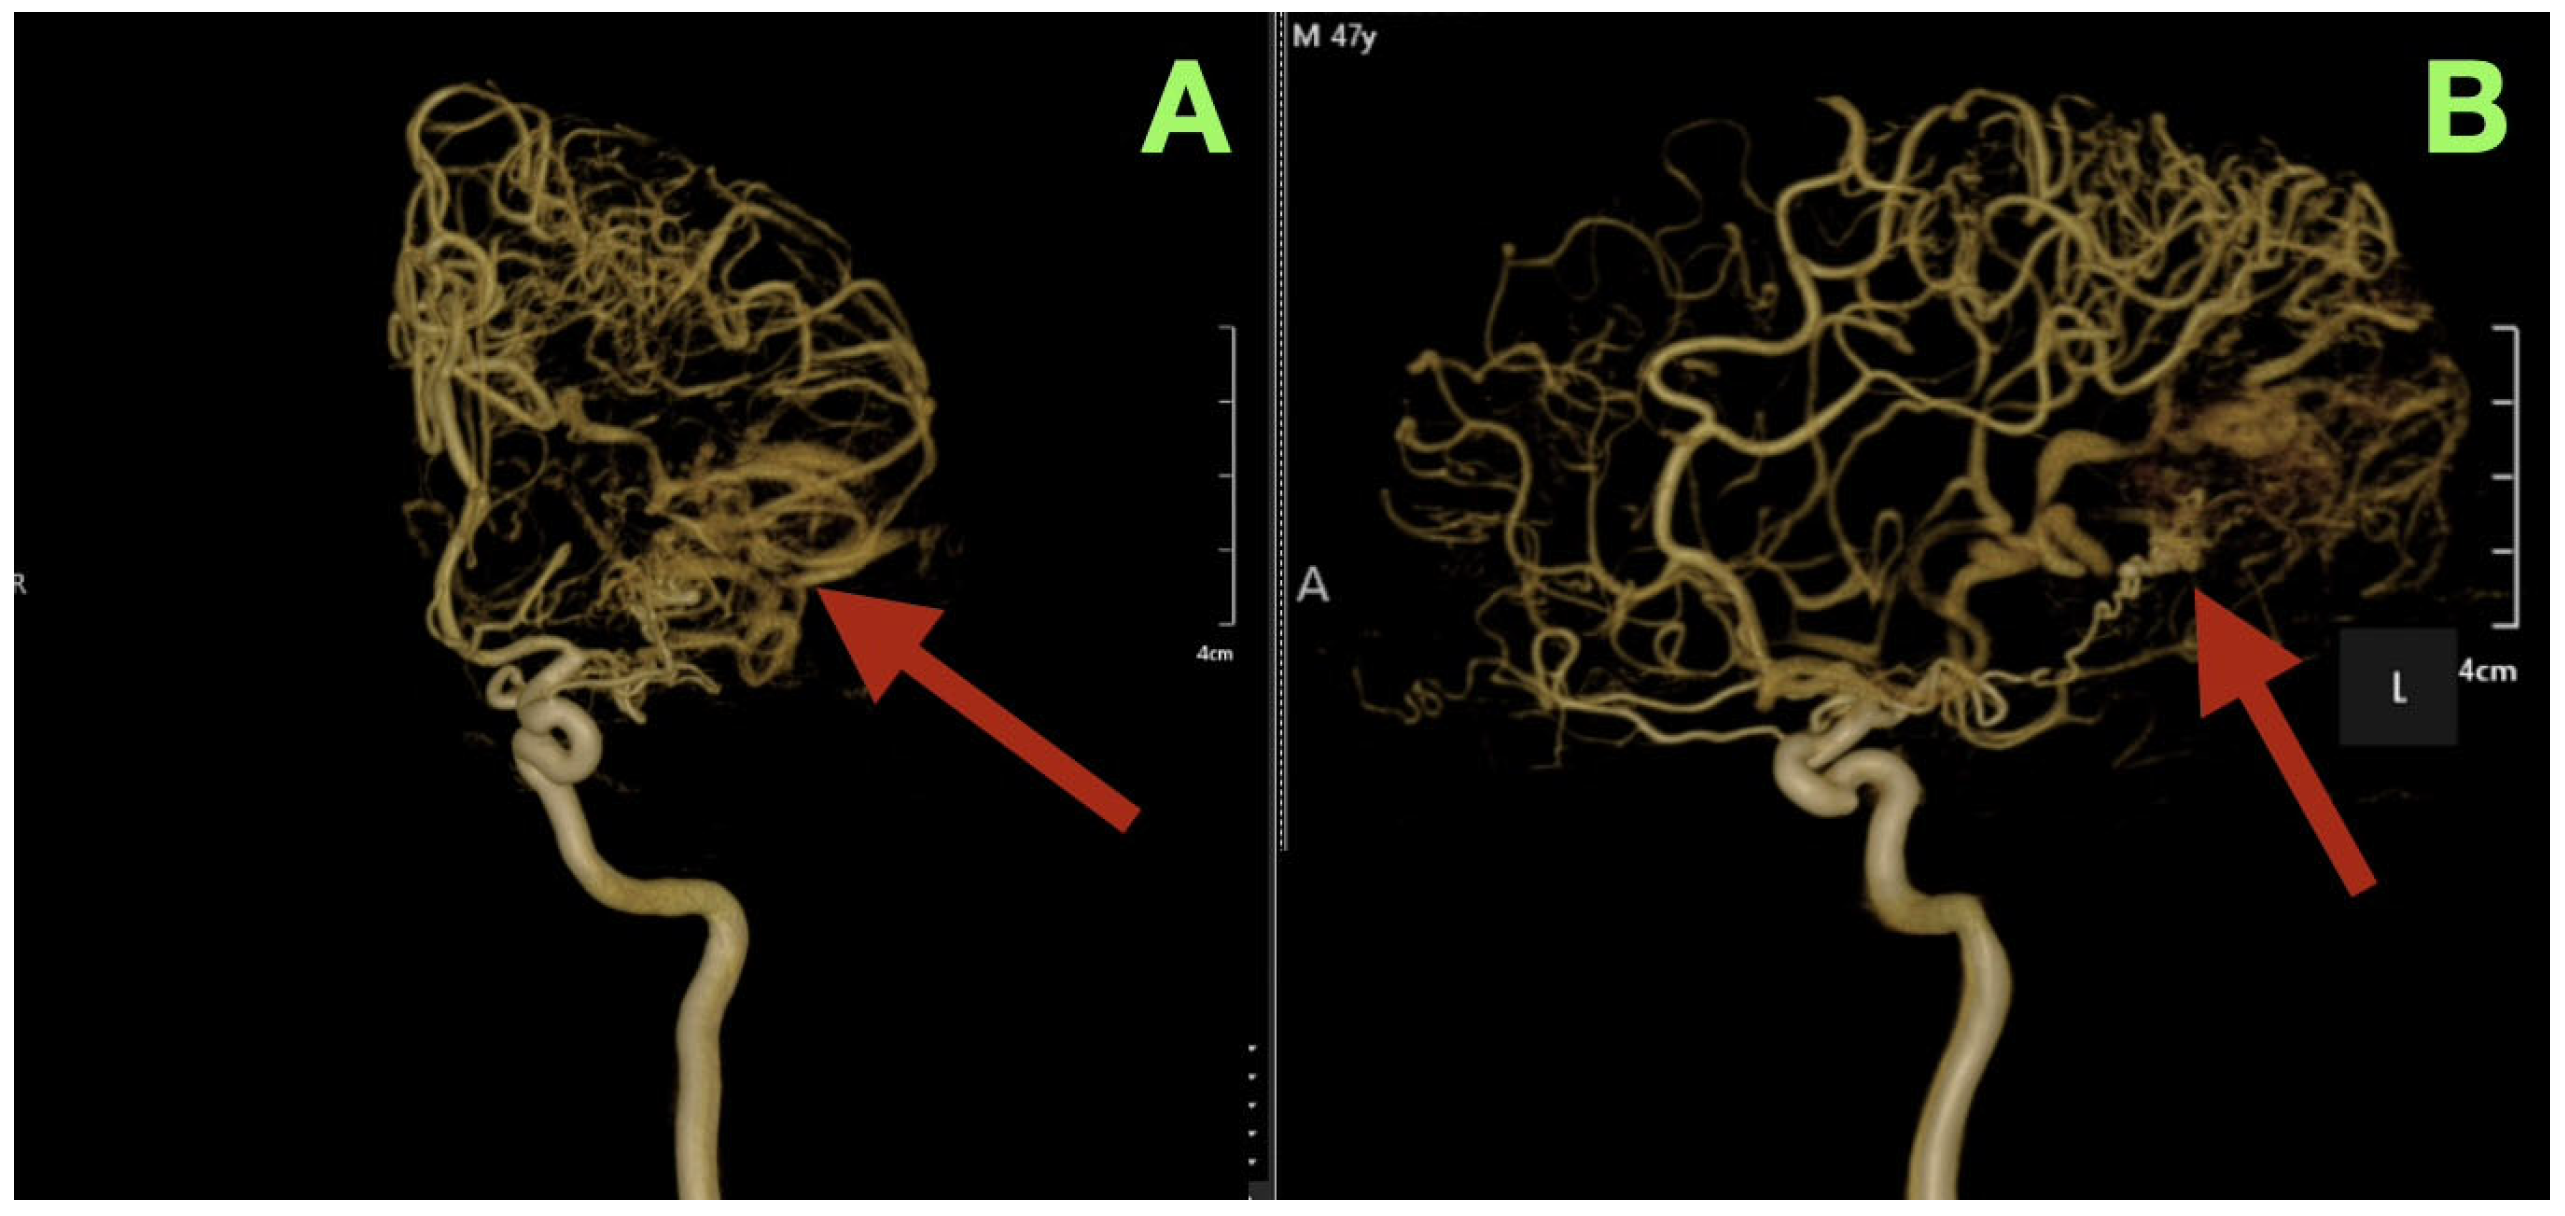

By the third postoperative day, the patient began to read and write spontaneously, and was participating in cognitive exercises with the speech therapy team. The patient demonstrated some subtle improvement in the speed of his speech and naming fluency, likely due to recovery of the cortex after relief of the venous hypertension secondary to the AVM. The cranial suture lines were clean, and the wound edges were beginning to show epithelialization. The patient was fully mobilized on the ward, and was able to converse and walk confidently. A cerebral angiogram immediately post-operatively (Figure 3) confirmed complete removal of the arteriovenous malformation. The antero-posterior and lateral views demonstrated no residual nidus, or early venous filling, and normal cortical perfusion through the middle and posterior cerebral artery distributions. The cortical veins filled symmetrically and drained normally into the superior sagittal and transverse sinuses. The flow pattern was normal, with no evidence of arteriovenous shunt or residual malformation.

Figure 3. Immediate postoperative digital subtraction angiography. (A): Frontal projection showing complete exclusion of the previously identified left temporo-parieto-occipital arteriovenous malformation (arrow). No early venous opacification or residual nidus is seen. (B): Lateral projection demonstrating normal cortical circulation and venous drainage through the superior sagittal and transverse sinuses (arrow). The vascular architecture is preserved and physiological, confirming complete anatomic and hemodynamic cure.